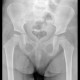

Pasien laki-laki berusia 4 tahun datang dengan keluhan kaki kanan terasa nyeri. Nyeri bertambah buruk ketika pasien berlari-lari. Pasien juga terlihat pincang pada kaki kanan ketika berjalan. Pasien dilakukan pemeriksaan rontgen dan ditemukan hasil rontgen berikut.

Apa diagnosis Dokter berdasarkan foto rontgen pasien?

Jawabannya Nekrosis avaskular kepala tulang femur kanan (Legg-Clave-Perthe Disease atau Penyakit Perthe)

Rontgen panggul menunjukkan kelainan pada kepala femur kanan dengan ruang sendi yang melebar dan kepala femur berbentuk baji yang pipih.

Hal ini sesuai dengan Legg-Clave-Perthe Disease (LCPD) yang merupakan nekrosis avaskular kepala femur idiopatik. Penanganan untuk anak-anak <8 tahun adalah pemberian analgesik, mengurangi beban berat badan, dan observasi (pengulangan rontgen setiap 4 bulan), karena memiliki potensi tinggi untuk remodeling tulang.

Aktivitas high impact harus dihindari seperti berlari dan melompat. Aktivitas low impact seperti berenang atau bersepeda dianjurkan. Pada LCPD, pembedahan (seperti osteotomi) umumnya dilakukan pada anak-anak yang berusia lebih dari 8 tahun atau mereka yang mengalami kolaps kepala femur yang sangat parah. Pada usia 4 tahun, potensi biologis pinggul untuk sembuh menjadi bentuk bulat dengan sendirinya sangat tinggi.